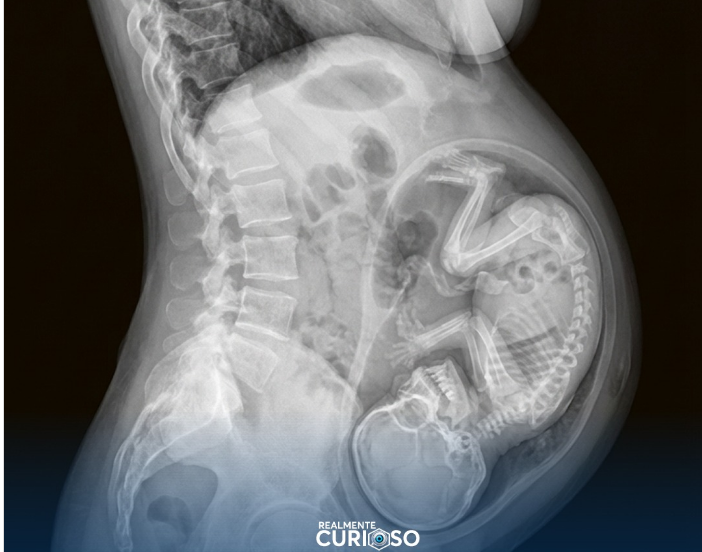

Durante a gestação, o cálcio que o bebê usa para formar seus ossos vem diretamente da circulação materna, que fornece esse mineral essencial por meio do sangue. Quando a demanda aumenta, o próprio organismo da mãe pode liberar cálcio dos seus ossos por um processo natural de reabsorção, garantindo que o feto receba o que precisa para se desenvolver. Essa adaptação faz parte da fisiologia normal da gravidez e ocorre para assegurar que a formação óssea do bebê aconteça de forma adequada, mesmo que a ingestão diária de cálcio da mãe não seja suficiente em alguns momentos.